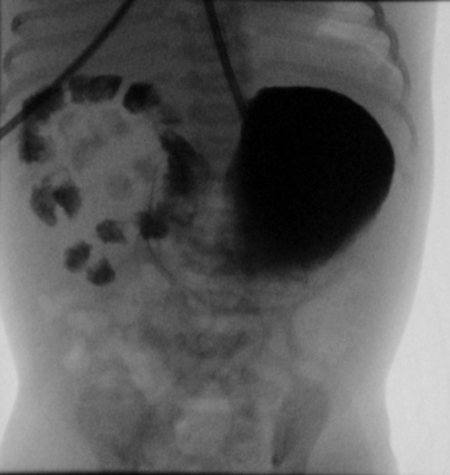

A full-term 2610g male neonate was admitted to the intensive care unit (NICU) with an antenatal history significant for a “double bubble” detected during the second trimester ultra sound examination (Fig. 1). A presumed diagnosis of duodenal stenosis/atresia was made with further karyotyping and anomaly scan showing no abnormalities. The antenatal imaging performed in the third trimester re-confirmed the findings of a double-bubble with no other anomalies being identified. Born at 38 +2/7 weeks, with APGAR scores of 7 and 9, the neonate had mild fullness of the right upper quadrant on clinical exam but no palpable mass. A supine abdominal x-ray revealed a dilated small bowel loop in the right upper quadrant with distal bowel gas, which was interpreted as a possible mega duodenum due to obstruction at that site consistent with the antenatal “double bubble” finding (Fig. 2). Patient then underwent an upper gastrointestinal series (UGI), which initially revealed no evidence of gastric outlet and duodenal obstruction or malrotation. However, subsequent delayed films showed of a space-occupying lesion in the right upper quadrant with a characteristic displacement of small bowel loops. Its subsequent opacification on delayed films was suggestive of a duplication cyst (Fig. 3). No evidence of bowel obstruction was seen. A post-natal ultrasound was not considered necessary in view of the findings on the UGI series.

Figure 1: 22wk prenatal US showing pseudo double bubble. |